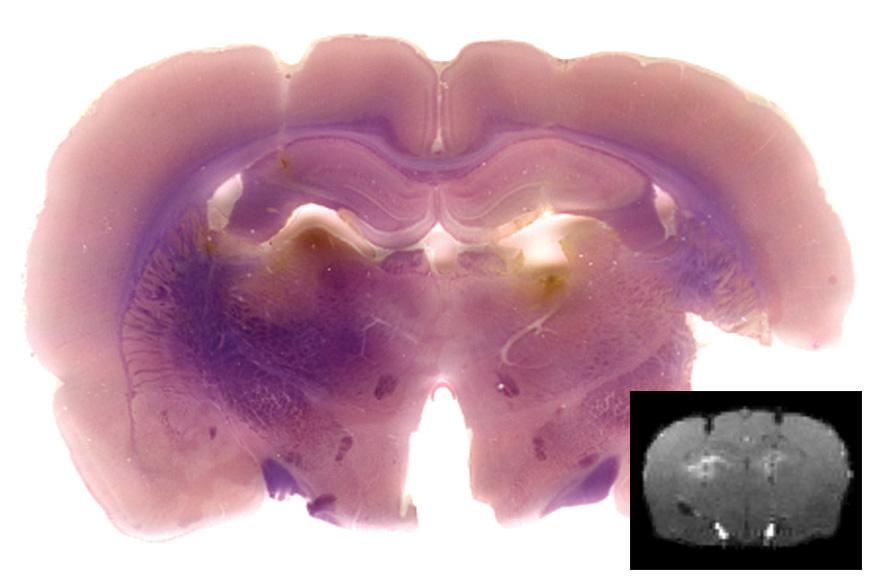

To help reach that goal, Jasanoff and colleagues have developed a new way to image a “reporter gene” — an artificial gene that turns on or off to signal events in the body, much like an indicator light on a car’s dashboard. In the new study, the reporter gene encodes an enzyme that interacts with a magnetic contrast agent injected into the brain, making the agent visible with MRI. This approach, described in a recent issue of the journal Chemical Biology, allows researchers to determine when and where that reporter gene is turned on.

The new MIT approach includes a contrast agent called a manganese porphyrin and the new reporter gene, which codes for a genetically engineered enzyme that alters the electric charge on the contrast agent. Jasanoff and colleagues designed the contrast agent so that it is soluble in water and readily eliminated from the body, making it difficult to detect by MRI. However, when the engineered enzyme, known as SEAP, slices phosphate molecules from the manganese porphyrin, the contrast agent becomes insoluble and starts to accumulate in brain tissues, allowing it to be seen.

The natural version of SEAP is found in the placenta, but not in other tissues. By injecting a virus carrying the SEAP gene into the brain cells of mice, the researchers were able to incorporate the gene into the cells’ own genome. Brain cells then started producing the SEAP protein, which is secreted from the cells and can be anchored to their outer surfaces. That’s important, Jasanoff says, because it means that the contrast agent doesn’t have to penetrate the cells to interact with the enzyme.

Researchers can then find out where SEAP is active by injecting the MRI contrast agent, which spreads throughout the brain but accumulates only near cells producing the SEAP protein.